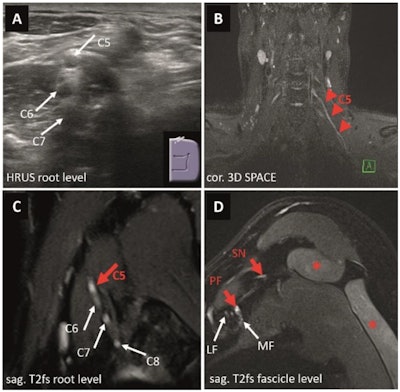

Images depict a 24-year-old male patient presenting with recurrent and exacerbating pain of his right shoulder with a difficulty to elevate (MRC 4+) his arm following a sports-related injury one year prior to imaging to rule out suspected plexus neuritis. On electrophysiology, only a borderline spontaneous activity pattern of the infraspinatus muscle was reported. On HRUS (A), the appearance of the supraclavicular plexus (dotted white line) was normal without suspicious alterations of nerve echogenicity or diameter. MRN of the proximal brachial plexus (B) suggested a possibly pathological T2 weighted signal increase at the conjunction of the inferior trunk (red dotted line) next to the unremarkable superior and middle trunk. However, there were no related clinical or electrophysiological findings. (C) Appearance of the distal, infraclavicular plexus segments including the lateral, medial, and posterior fascicles was normal as well as the suprascapular nerve. (D) No signs of muscular denervation of the supra- or infraspinatus muscles (*) were present on MRN. Therefore, a plexus neuritis or another nerve-related etiology was ruled out. An artificial signal increase, often caused by the magic-angle artifact, can lead to false-positive results on MRN and must be taken into consideration when interpreting MRN examinations. Images and caption courtesy of the RSNA.Images depict a 24-year-old male patient presenting with recurrent and exacerbating pain of his right shoulder with a difficulty to elevate (MRC 4+) his arm following a sports-related injury one year prior to imaging to rule out suspected plexus neuritis. On electrophysiology, only a borderline spontaneous activity pattern of the infraspinatus muscle was reported. On HRUS (A), the appearance of the supraclavicular plexus (dotted white line) was normal without suspicious alterations of nerve echogenicity or diameter. MRN of the proximal brachial plexus (B) suggested a possibly pathological T2 weighted signal increase at the conjunction of the inferior trunk (red dotted line) next to the unremarkable superior and middle trunk. However, there were no related clinical or electrophysiological findings. (C) Appearance of the distal, infraclavicular plexus segments including the lateral, medial, and posterior fascicles was normal as well as the suprascapular nerve. (D) No signs of muscular denervation of the supra- or infraspinatus muscles (*) were present on MRN. Therefore, a plexus neuritis or another nerve-related etiology was ruled out. An artificial signal increase, often caused by the magic-angle artifact, can lead to false-positive results on MRN and must be taken into consideration when interpreting MRN examinations. Images and caption courtesy of the RSNA.